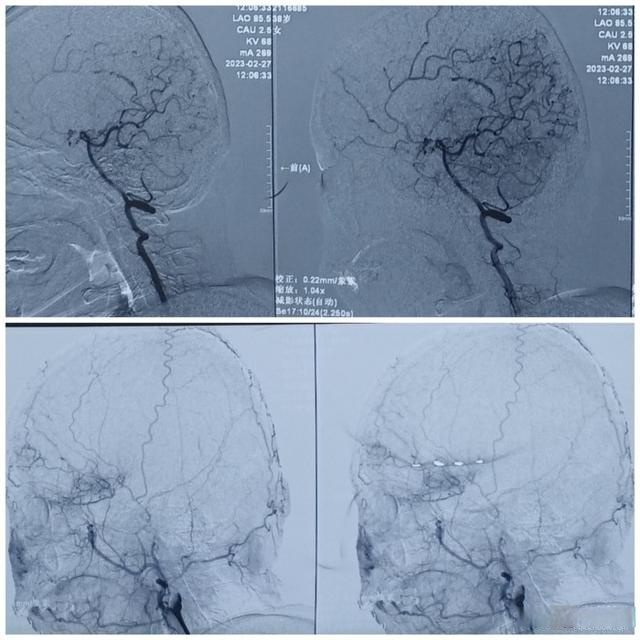

烟雾病到底是一种什么样的病,它与脑梗塞有何不同?孙雷涛给出了解释:烟雾病是一种以双侧颈内动脉末端及大脑前动脉、大脑中动脉起始部慢性进行性狭窄或闭塞为特征,并继发颅底异常血管网形成的一种脑血管疾病,由于这种颅底异常血管网在脑血管造影图像上形似“烟雾”,故称为“烟雾病”。

征得患者家属同意后,滨医附院神经外科为这名39岁“脑雾病”患者实施脑动脉搭桥及颞肌脑贴敷联合脑血运重建手术,在麻醉科医师、电生理监测医师通力配合下,历时三个多小时,手术取得圆满成功。目前患者术后恢复良好,脑灌注缺血情况有了明显改善。